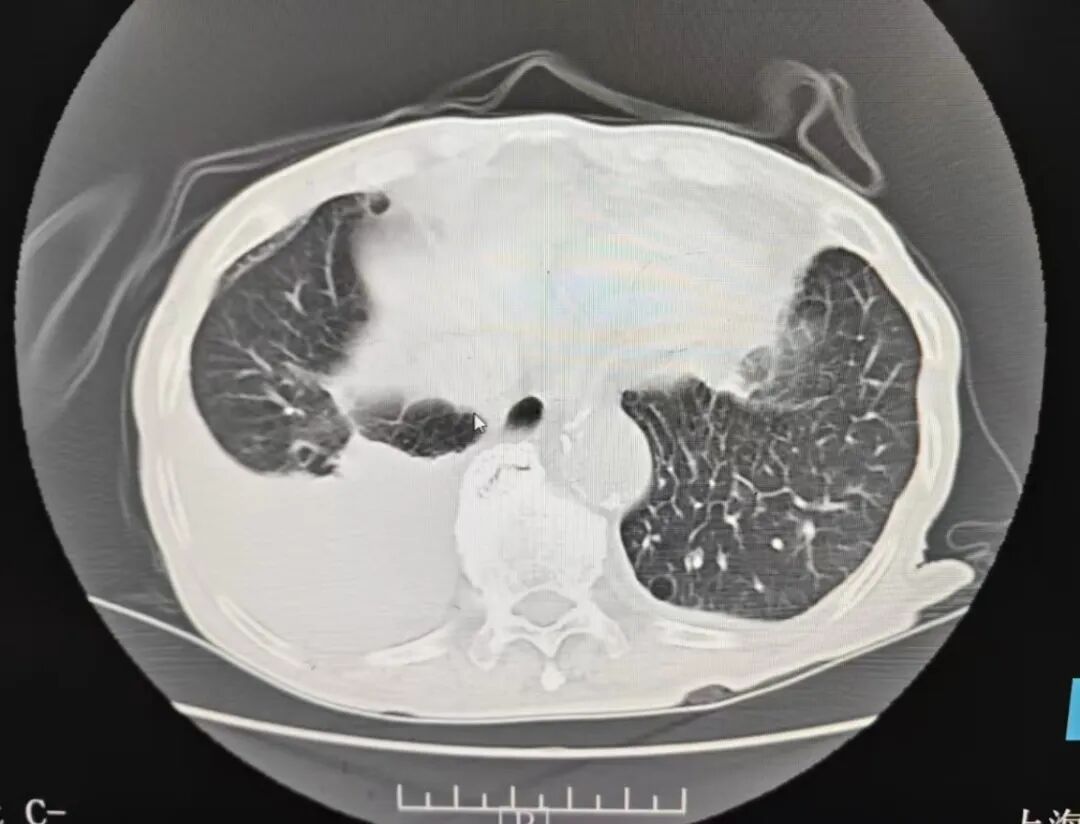

王爷爷在家人的陪同下,来到奉贤区中医医院急诊就诊。医生为他进行初步的检查,检查结果显示,王爷爷的心影增大,右侧有胸腔积液。

经过12天的系统治疗,王爷爷的症状显著改善:活动后偶尔有胸闷气短症状出现,比较之前好转了很多,夜间再也没有因为胸闷憋醒需要坐起来的情况,一阵阵的心慌消失了,咳嗽咳痰也没有了,双下肢水肿完全消退。复查的心衰指标、心电图、胸腔积液情况都明显好转。